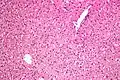

Micrograph showing ground glass hepatocytes. H&E stain. -

In liver pathology, a ground glass hepatocyte, abbreviated GGH, is a liver parenchymal cell with a flat hazy and uniformly dull appearing cytoplasm on light microscopy. The cytoplasm's granular homogeneous eosinophilic staining is caused by the presence of HBsAg.

The appearance is classically associated with abundant hepatitis B antigen in the endoplasmic reticulum, but may also be drug-induced.[1][2] In the context of hepatitis B, GGHs are only seen in chronic infections, i.e. they are not seen in acute hepatitis B.